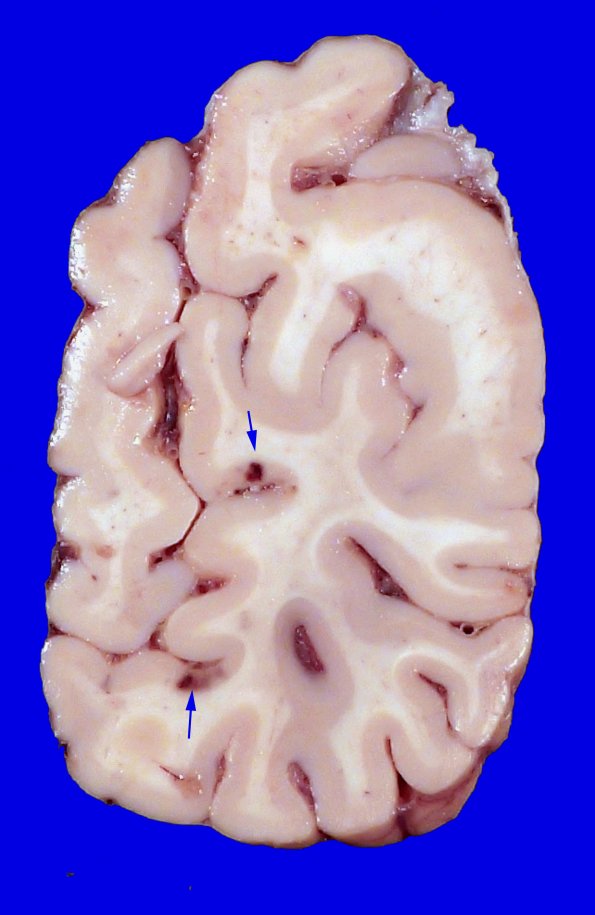

23F3,4 Additional lesions are illustrated in the cerebral hemispheres.